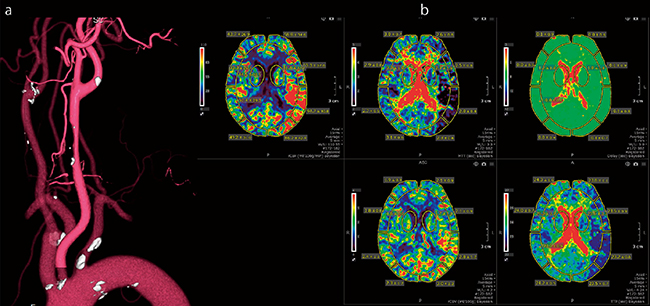

■頸動脈狭窄により灌流異常を呈したperfusion例(CT)

総頸動脈の狭窄所見と頭蓋内灌流異常を1回の検査で検出

a:頸部3D-CTA b:perfusion map(上段左からCBF、MTT、Delay、下段左からCBV、TTP)

Vitreaの“Brain Perfusion Bayesian” は、ベイジアンアルゴリズム(ベイズ推定法)を用いた灌流画像解析アプリケーションで、従来のSVD法の課題だったさまざまなノイズ因子の影響を低減し、より精度の高い解析が可能になった。脳血流量(CBF)、脳血液量(CBV)、平均通過時間(MTT)など5種類のマップのほか、サマリーマップにより虚血性コアと思われる部分とペナンブラと思われる部分の確認が行える。後藤主任は、「サマリーマップでは、虚血が示唆される範囲が画像と数値で表示できるので、血栓回収療法が有効かどうか、より的確な判断のためのデータを提供できます」と述べる。

PSCでの急性期脳卒中症例ではMRファーストが基本だが、脳梗塞で発症から時間が経過し、血栓回収療法の適応があるかを確認する場合にはCTを撮影している。Aquilion ONEではダイナミックボリュームスキャンを行い、Vitreaでperfusion画像と4D-CTAを作成している。後藤主任は急性期脳梗塞の運用について、「Aquilion ONEで撮影したデータをVitreaに転送することで、perfusion解析と同時に4D-CTAを簡易的に作成することが可能です。これによって血管の走行なども確認できるので、虚血領域を表示して側副血行路の有無を確認できます。ここまでを、Vitreaに転送してから2分弱で解析できるので、急性期の脳梗塞の確認に必要な情報を短時間で提供できます」と評価する。